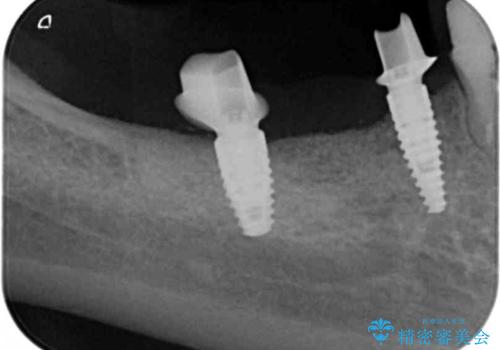

狭小な歯槽骨に対するインプラント治療

- 歯を失い噛めないこと、骨の幅が狭く他院でインプラント治療が難しいと断られ、当院でのインプラント治療が可能かどうか相談来院されました。

骨の造成、角化歯肉の移植を行いインプラント周囲の環境を整えた治療を計画します。